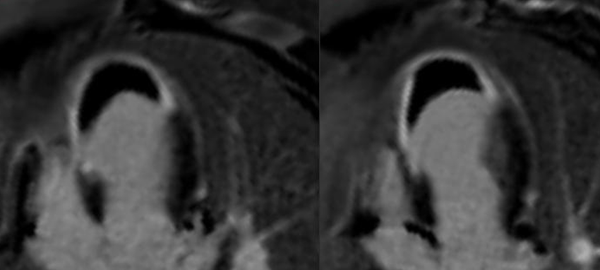

This 57-years old presented with acute chest pain. She was diagnosed to have a non-STEMI infarct. Coronary angiography and echo were done. Based on the echo findings, an MRI was done, which uncovered a myriad of findings.